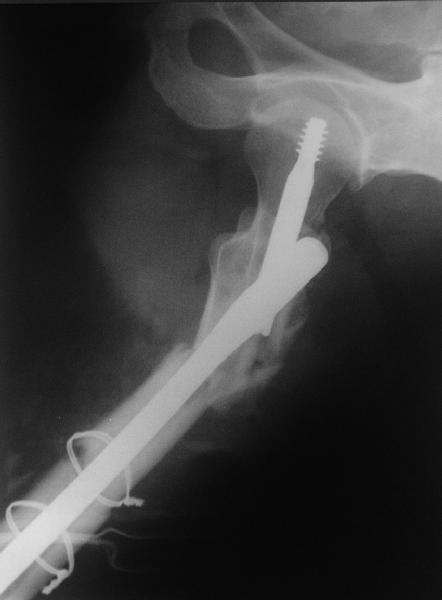

ВБ> Длинная гамма?

ВБ> Зона раскола во время моей ревизии проходит по боковой поверхности как

ВБ> раз в зоне введения шеечного винта (картина как топор разрубил полено

Зона введения и вообще латеральная стенка тут не имеет значения, поскольку угловая стабильность обеспечивается самим фиксатором.

В общем, сделали. См. приложение.

Длина и из-за этого ось получились не совсем такие, как хотелось бы, все-таки срок после той операции уже 6 недель. Может быть, стоило провести дистракцию аппаратом неделю-другую. Заранее спасибо за комментарии и критику.